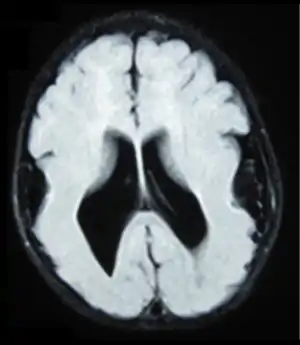

Lissencephaly (meaning "smooth brain")[1] is a set of rare brain disorders where the whole or parts of the surface of the brain appear smooth.[2] It is caused by defective neuronal migration during the 12th to 24th weeks of gestation resulting in a lack of development of brain folds (gyri) and grooves (sulci).[3] It is a form of cephalic disorder. Terms such as agyria (no gyri) and pachygyria (broad gyri) are used to describe the appearance of the surface of the brain.

| Lissencephalic brain of a human, lacking surface convolutions (Gyrification) | |